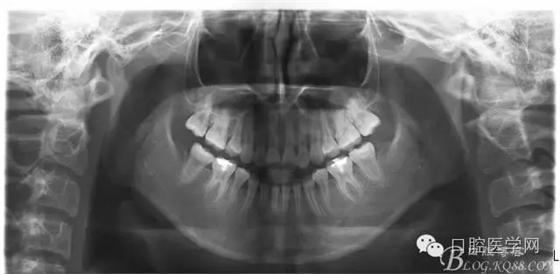

查:右側(cè)第二前磨牙第一乳磨牙恒尖牙頰側(cè)前庭溝隆起,捫有乒乓球感。曲斷及CT示:右側(cè)第二前磨牙第一乳磨牙恒尖牙根尖區(qū)有一囊腫,頰舌側(cè)骨板極薄,牙根無吸收,第二前磨牙牙根位于囊腫中,第一雙尖牙牙冠遠(yuǎn)中水平向阻生,牙冠位于囊腫中。經(jīng)協(xié)議:手術(shù)摘除創(chuàng)傷大,同意開創(chuàng)引流保守治療。

否認(rèn)手術(shù)禁忌癥及過敏史。消毒,局麻下鋪巾,拔出第一乳磨牙,有囊液溢出,擴(kuò)大開放引流孔,取部分囊壁送病理,生理鹽水沖洗,置引流管縫合固定。病理報告:囊腫。八月后局麻拔除第一雙尖牙刮凈剩余變小的囊壁。

術(shù)后一個月 三個月 五個月 八個月 拔除第一雙尖牙后曲斷片: